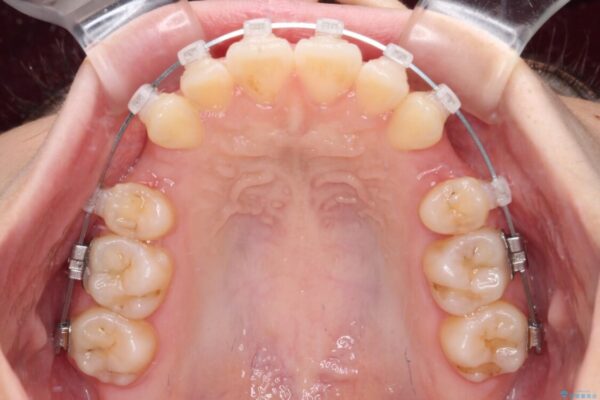

治療途中

• 【モニター】口が閉じられない ワイヤー装置での抜歯矯正 治療途中画像

※写真にある上顎装置はメタルブラケットではありません。メーカー在庫都合などにより別の装置を使用しております。

舌の突出癖があり、前歯の移動量も多くなるため、治療期間は長くなると予想されましたが、13ヶ月という予定の半分程度の期間で終えることができました。